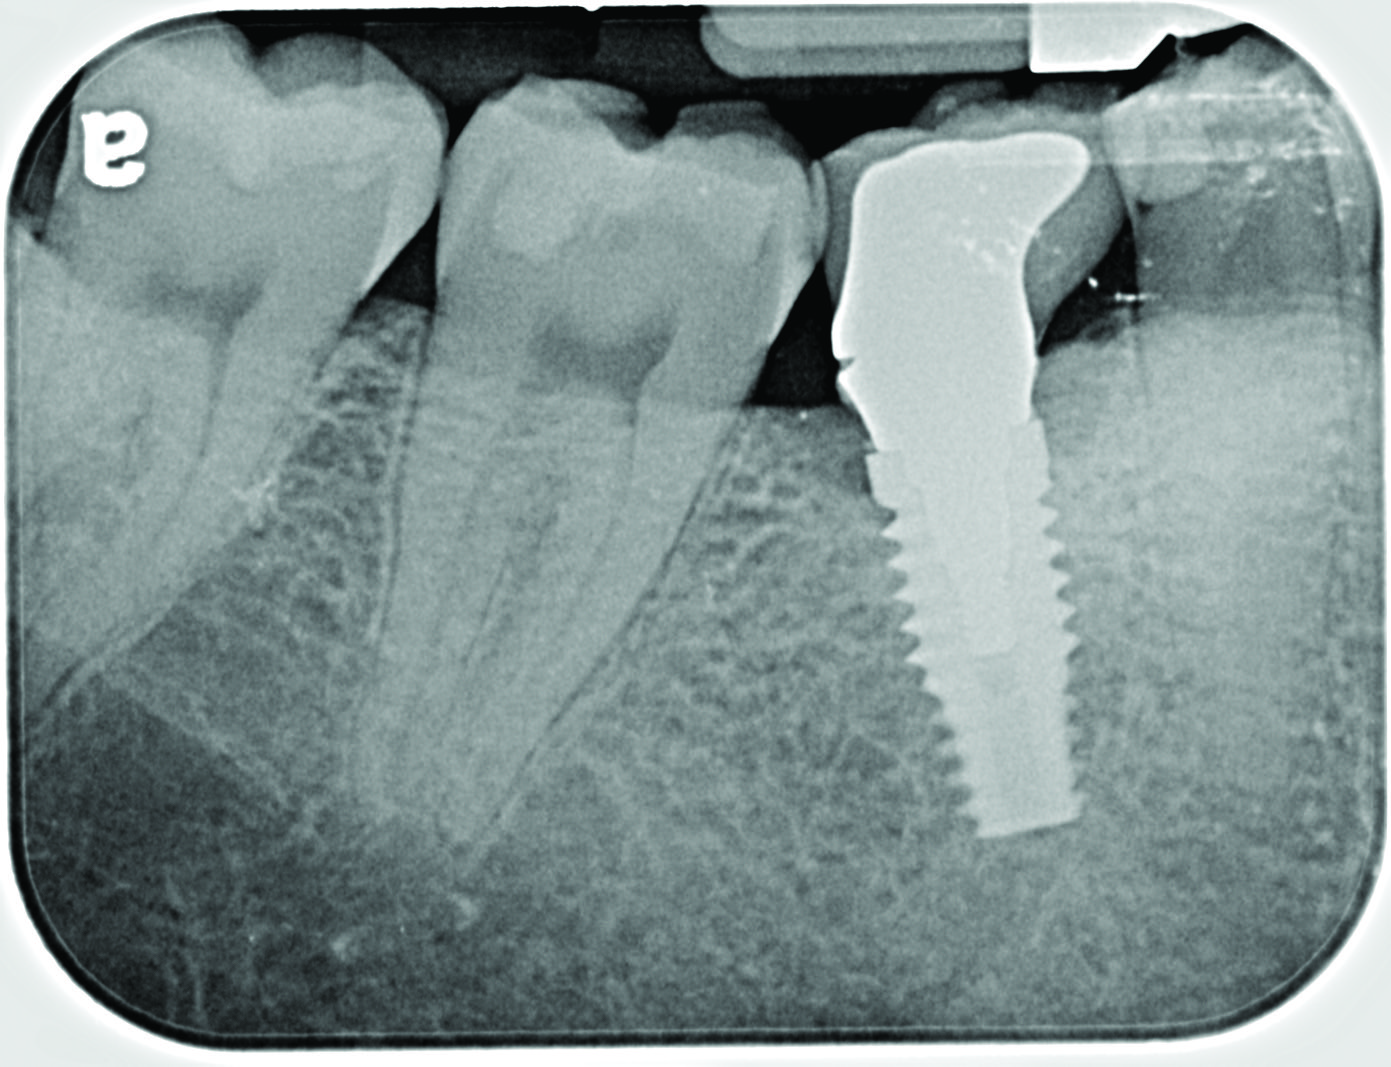

Fig 13. Radiograph depicting peri-implantitis.

Figure 13

Excess Cement Leading to Peri-implantitis

If all implant-supported crowns could be designed for screw retention, no discussion of excess cement would be necessary. However, screw retention is not always possible depending on the location of the access opening and because of the unesthetic appearance in anterior restorations or the mesial/distal angulation of the implant compromising the path of insertion (Figure 12). Residual cement left after crown cementation on implants can lead to peri-implant inflammation, peri-implantitis, and eventual loss of the implant (Figure 13 through Figure 15).25 The presence of lingering excess cement can encourage the development of bacterial colonization and peri-implantitis. Conversely, when too little cement is used, voids in the cement layer can occur and the prosthesis can become loose.26 The deeper the implant crown margin, the more difficult it is to remove excess cement.27

Radiopaque cements that contain zinc phosphate and zinc oxide (with and without eugenol) should be considered to help identify excess interproximal cement; however, this should be used secondarily to proper margin height and careful removal of cement during cementation. Resin cements lack the same opacity as zinc-containing cements and have been shown to be the most difficult to remove.28 Often in the process of removing this excess cement, the abutment surface becomes scratched and damaged, potentiating further plaque accumulation.29

Several modifications in abutment design and cementation have been suggested. Placing vent holes in the abutment during fabrication or leaving most of the screw-access chamber open for access has reduced the amount of cement that expresses out into the sulcus.26 It is also beneficial to extraorally express excess cement on an abutment replica prior to final crown seating to minimize complications. If retrievability is desired with cementable implant crowns, weaker cements (eg, zinc oxide eugenol) should be used first and progressively changed until the desired retention is achieved.